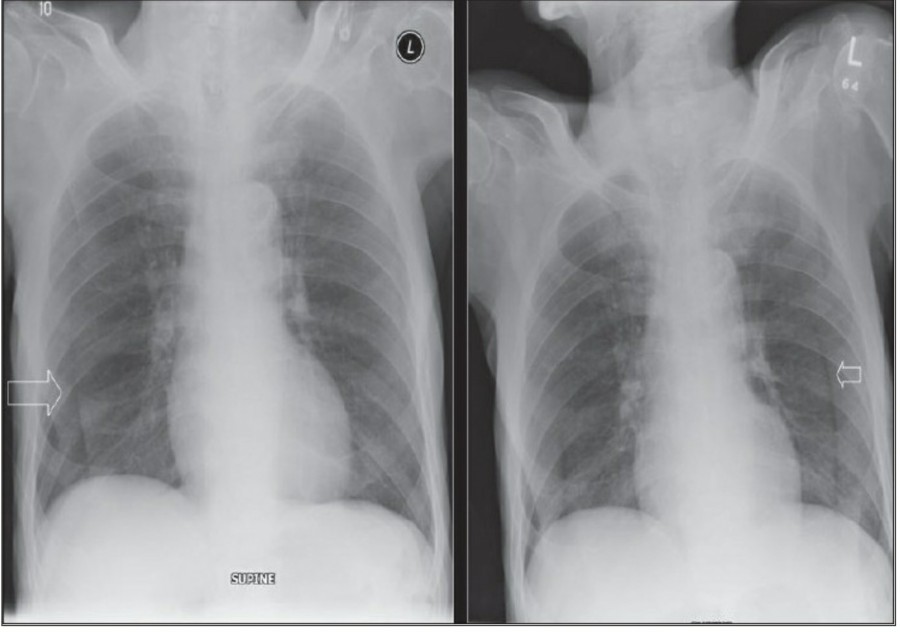

방사선 소견상 Pleural effusion은 환자 흉부의 dependent area에 고인다. Erect position에서 확인하기가 쉬운데, 폐의 base에 고임으로써 costophrenic angle blunting을 보이고 lower lobe vessel들의 흐리게 한다. Supine position에서는 확인이 더 어려운데, pleural fluid는 posterior basilar space에 고여서 폐 base 쪽으로 intensity가 증가하는 homogenous density를 보인다. 정상적인 bronchoalveolar marking은 이와 같은 veil-like density 안에서 확인 가능하다. Fluid 양이 늘어나면서 diaphragm의 윤곽이 흐릿해지고 costophrenic angle도 없어지는데, 이 costophrenic angle blunting이 없더라도 pleural space에 1L 정도의 pleural fluid가 있을 수 있다는 것을 기억해야 한다. 그 양이 더욱 늘어날 수록 fluid는 lung의 apex에서 pleural cap으로 나타날 수 있으며, 이는 supine position에서도 확인 가능하다. Pleural fluid는 lung의 medial side에 고일 수도 있으며 이는 mediastinum의 확장으로 보일 수도 있다.

적은 양의 pleural fluid는 꼼꼼히 확인하더라도 supine radiograph에서 놓칠 수 있는데, 만약 chest X ray에서 보이지 않지만 임상적으로 의심이 되는 경우에는 lateral decubitus film으로 확인해 볼 수 있다. Fluid는 dependent position에 고이므로 환자를 의심되는 방향으로 옆으로 눕혀야 한다. Lateral decubitus film은 적은 양의 pleural fluiid는 물론이고 loculated effusion과 free effusion을 확진하는 데도 도움이 된다. 특히 loculated effusion은 한 개 이상의 drain이 필요할 수 있으므로 pleural drainage를 고려할 때 특히 중요한 검사이다. 중환자에서 흔하게 나타나는 subplumonic effusion은 lung base에 존재하는 pleural effusion을 말하는데, chest X ray 상에서 raised hemidiaphragm with flattening and lateral displacement of the dome 형태로 나타나며, lateral decubitus film이 도움이 된다.